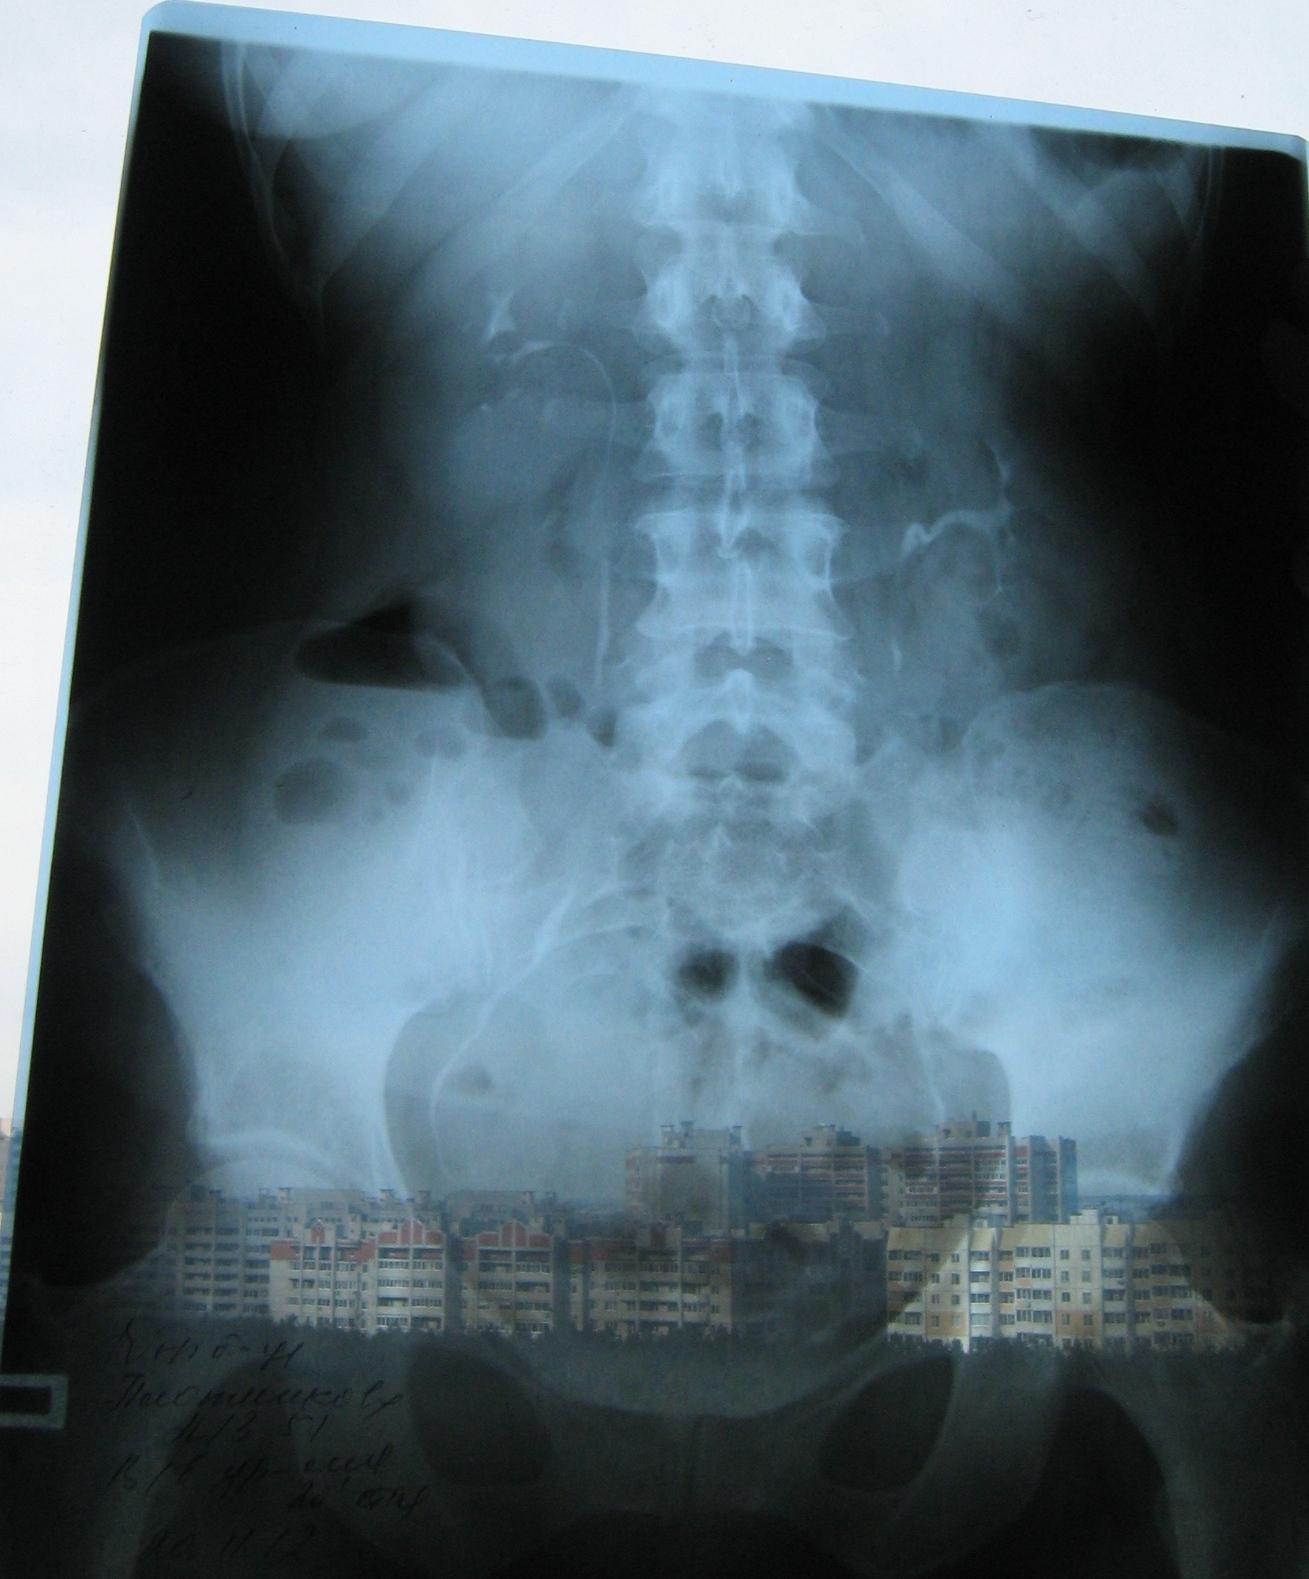

Была сделана операция 04.07.2012г по поводу нефропексии правой почки поясничной мышцей с помощью разреза. После операции болит правая сторона живота и в спине и в пояснице был затронут нерв, и до сих пор правая нога до колен не отходит спереди и сбоку. Через полтора месяца после операции образовался отек, пошло воспаление сзади на спине, потому что был затронут нерв. Сделала урографию через 4 месяца после операции. Если вас не затруднит, посмотрите пожалуйста снимки, правильно ли располагается мочеточник правый после операции. Скажите пожалуйста, посмотрев мои снимки, правильное ли расположение мочеточника и почему болит правая сторона живота все это время, и каким исследованием теперь после операции проверить что там творится в животе, что там затронуто? Все указывает на то что был затронут нерв, оперирующий врач говорит что не может быть такого, а я уже почти всю ногу правую не чувствую

Снимки прикрепляю

Абсолютно нормальное расположение почки и мочеточника . Но ведь и онемение нижней конечности с положением почки не связано. Есть такое понятие "футлярный синдром"- после вынужденного положения конечности. Проконсультируйтесь с неврологом.